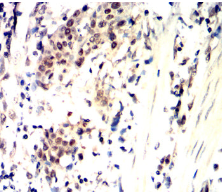

CDK4 Mouse Monoclonal antibody[4A11E]

IHC    1/200 - 1/1000